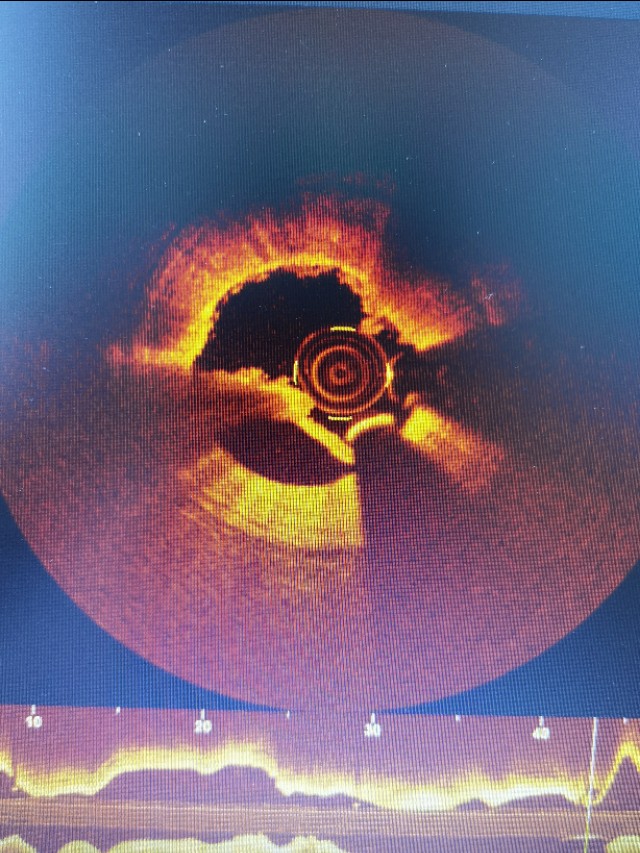

我院心内一科在袁俊强主任,徐谭副主任的带领下,在信阳市率先引入IVUS,血管旋磨,FFR,生物可吸收支架等众多新技术后,再引入光学相干断层显像术(OCT)。目前已应用自主技术完成OCT检查多例,为冠心病患者提供更准确的诊断和更优质的治疗。

OCT又称“光学活检”,是血管内超声(IVUS)的光学同类技术,但与IVUS相比,高分辨率的OCT可在近似于组织学水平上,诊断和评价冠状动脉斑块,从而使医生更好地理解冠状动脉疾病的病理学特点,并针对不同患者的自身特点进行个体化治疗。